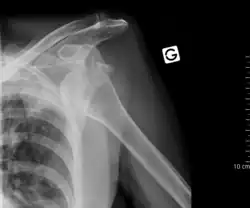

Luxação do ombro ou luxação da articulação do ombro é um deslocamento (luxação) da articulação do ombro. A luxação do ombro é uma das mais frequentes luxações de grandes articulações.

Ela pode ser causada através de um acidente (luxação traumática) ou por sua concepção predisponente (luxação habitual). Os sintomas são uma restrição da mobilidade da articulação do ombro, dores e alteração do formato do ombro. A terapia baseia-se em uma reposição, após a exclusão de fraturas ósseas através de um raio-x.

Através de raio-x em diversos planos confirma-se o diagnóstico e uma fratura pode ser descartada. Pode ser solicitada uma ressonância magnética para ser descartada uma lesão Bankart.